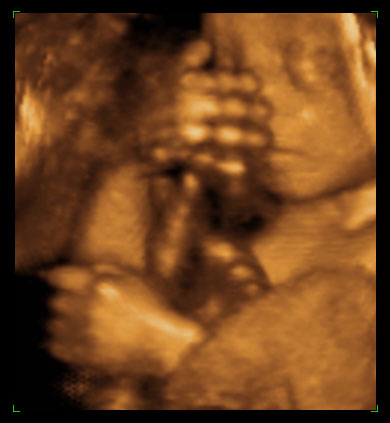

ултразвучни приказ бебе 24. недеље трудноће (1)